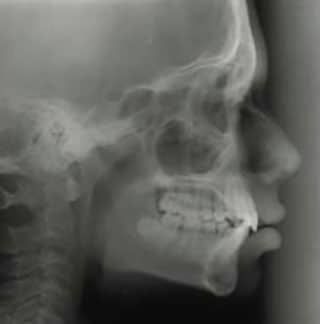

5. Radiographie céphalométrique

Une projection céphalométrique est une radiographie dentaire d’un côté de la tête entière. Les orthodontistes l’utilisent souvent pour voir comment les dents et les os des mâchoires s’ajustent afin de mieux créer un plan de traitement qui implique toute la bouche.

Votre dentiste peut également vous suggérer ce type de radiographie pour diagnostiquer toute complication de la gorge, telle que des grosseurs ou un cancer. Enfin, si vous souffrez d’apnée du sommeil, les dentistes peuvent souvent vous aider. En effet, il peut d’abord vous suggérer une radiographie céphalométrique pour voir clairement la structure de votre gorge et déterminer la cause de votre apnée du sommeil.